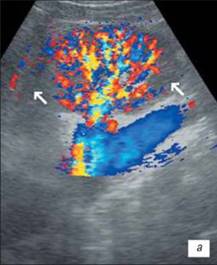

УЗІ нирки при запальних змінах в режимі ЦДК

а – інтраренальний судинний малюнок нирки збережений, кортикальный кровотік визначається у всіх відділах паренхіми;

б – збіднення судинного малюнка;

в – швидкісні показники в гирлі ниркової артерії в межах вікової норми: Vps– 83,7 см/с; Ved– 34,1 см/с; RI– 0,63; PI– 0,96.

На розгорненій картині УЗІ з ЦДК характеризується нерівністю, нечіткістю, деформацією контура нирки, який місцями може не простежуватися; нирка іноді місцями погано диференціюється від навколишніх тканин, що утрудняє визначення її розмірів; візуалізуються дрібні, неправильної форми втягнення контура, розподілені або по всьому контуру, або в якомусь фрагменті нирки; визначається нечіткість кортико-медуллярной диференціювання; є виражені дифузні зміни паренхіми нирки з помірним нерівномірним підвищенням її эхогенності; дилатація чашечно-мискової системи; фрагментарне стоншування паренхіми нирки з компенсаторним потовщенням або збереженням товщини інших її ділянок помірне збіднення інтраренального судинного малюнка, найбільш виражене в місцях деформації і втягнення контура нирки; зниження швидкісних характеристик артеріального кровотоку (мал. 3).